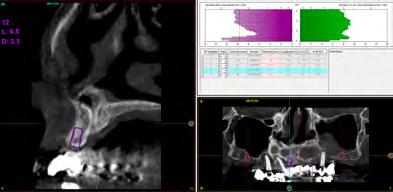

Figura 8-11. Imágenes de la planificación del cone-beam dentral tras el cierre de los tejidos blandos (inserción temprana de los implantes). En ellos observamos la planificación de los implantes de 6.5 mm de longitud y de diámetro reducido y plataforma 3.0 que van a ser empleados.

Dentista y Paciente 18 Calidad y dirección